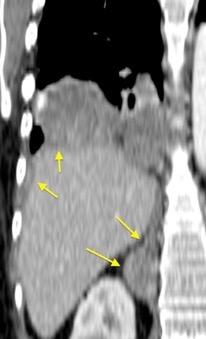

T. mixto de células germinales del testículo izquierdo

Nódulos pulmonares múltiples. (flechas verdes). Masas paratraqueales. (flechas amarillas). Dudoso ensanchamiento retrocrural (flechas negras). sigue….

Ttawfik A et al. Trans-diaphragmatic Pathologies: Anatomical Background and Spread of Disease on cross-sectional Imaging. Current Problems in Diagnostic Radiology. 2021.

T. mixto de células germinales del testículo

izquierdo Metástasis pulmonares. (flechas verdes). Ganglios paratraqueales. (flechas amarillas). Ganglios retroperitoneales (flechas negras)

Tawfik A et al. Trans-diaphragmatic Pathologies: Anatomical Background and Spread of Disease on cross-sectional Imaging. Current Problems in Diagnostic Radiology. 2021.